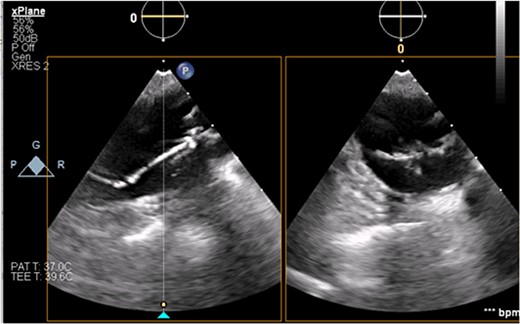

The patient’s milrinone dose was unable to be increased due to his risk for VT and his marginal blood pressures. A 50 cc 8 French left axillary IABP with proximal and distal markers was placed under fluoroscopy and transesophageal echo (TEE) guidance to prevent worsening of end-organ dysfunction and cardiogenic shock. About 3.5 weeks later, the patient received a heart transplant. His 20 gauge right radial arterial catheter was used for monitoring. There were no identifiable changes in the arterial line and the pressure waveforms. The patient was ambulatory in the intensive care unit (ICU) and showed no signs of decreased perfusion. After induction of general anesthesia, TEE showed the IABP in his aortic arch and ascending aorta with its tip placed proximally in the descending aorta (Figs 1 and 2).

Transesophageal image of the aortic root and ascending aorta with IABP present.

Transesophageal image of the ascending and descending aorta with mispositioned IABP present.